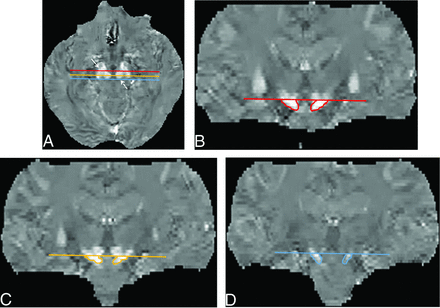

To measure the S value of the SN, we used coronal multiplanar reconstruction images to place an ROI in the SN with reference to the Schaltenbrand and Wahren atlas.36,37 We selected 3 coronal multiplanar reconstruction images at the level of the anterior, middle, and posterior edges of the RN on axial images to measure the spatial susceptibility differences in the anterior, middle, and posterior parts of the SN (aSN, mSN, and pSN) (Fig 2). To avoid contamination by the subthalamic nuclei,36,37 we placed ROIs on the aSN, mSN, and pSN inferior to the caudal edge of the RN (Fig 2). The averaged value of the aSN, mSN, and pSN was defined as the value of the whole SN.

ROIs on the substantia nigra on QSM images. Multiplanar reconstruction coronal images were selected at the 3 planes, that is, the anterior (red line), middle (light orange line), and posterior (blue line) edges of the red nucleus on axial QSM images (A), to measure spatial susceptibility differences in the anterior, middle, and posterior parts of the SN. To avoid contamination by the subthalamic nuclei, we placed an ROI on the aSN (B), mSN (C), and pSN (D) below the caudal edge of the RN on coronal QSM images. The averaged value of the aSN, mSN, and pSN was defined as the value of the whole SN. Solid arrow indicates the SN; dotted arrow, the RN.